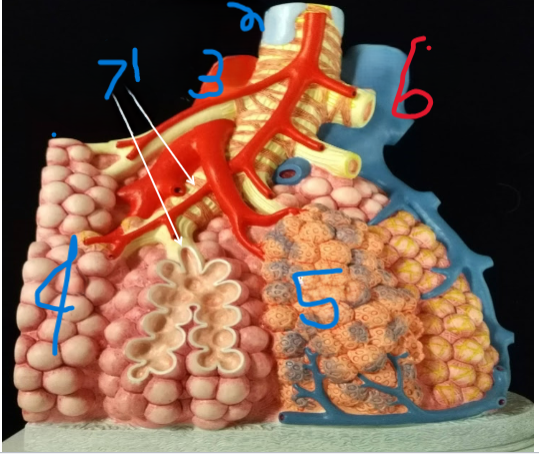

Terminal Bronchiole

What is depicted by #1

Bronchiole with smooth muscle

What is depicted by #2

Pulmonary vein, branch

What is depicted by #3

Alveoli

What is depicted by #4

Pulmonary capillaries

What is depicted by #5

Pulmonary artery, branch

What is depicted by #6

Respiratory Bronchiole

What is depicted by #7